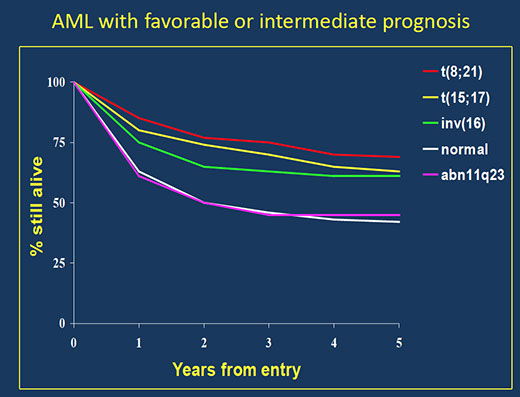

Acute myeloid leukemia (AML) with recurrent genetic abnormalities

- Acute myeloid leukemia with t(8;21)(q22;q22.1); RUNX1-RUNX1T1

- Acute myeloid leukemia with inv(16)(p13.1q22) or t(16;16)(p13.1;q22); CBFB-MYH11

- Acute promyelocytic leukemia (APML) with PML-RARA

- Acute myeloid leukemia with t(9;11)(p21.3;q23.3); KMT2A-MLLT3